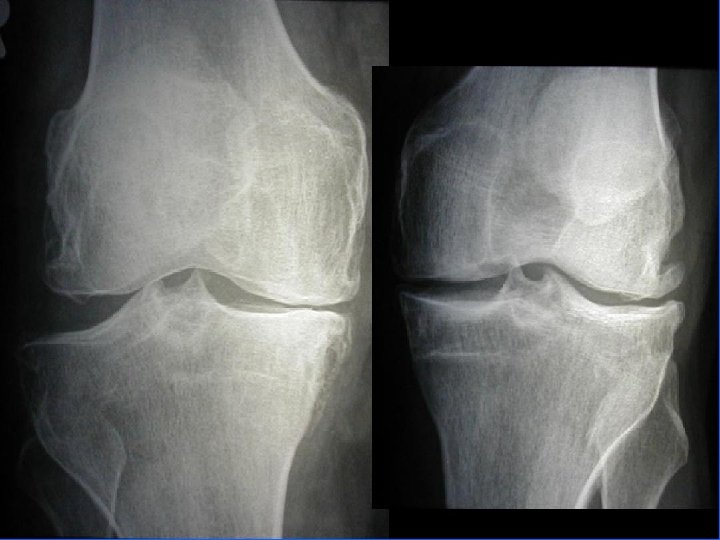

Arthrose fémoro-tibiale Iconographie • Radiographie : – Face en appui bipodal – Profil – Schuss (face en charge à 30° de flexion) pour compartiment post • Signes: – Pincement interligne – Ostéophytose – Ostéosclérose sous-chondrale avec géodes